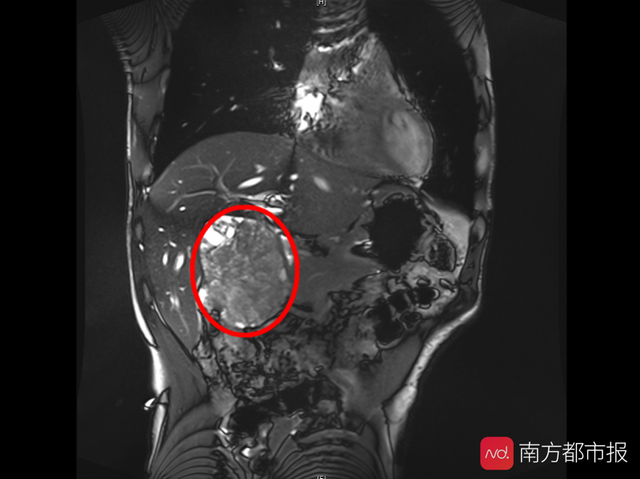

胆囊癌能活多久(胆囊癌注定只有3个月命广州这家医院帮他逆天改命)

去年底被诊断为胆囊癌,病情严重到不得不中途终止手术,且预期寿命不超过3个月。通过中山大学孙逸仙纪念医院肝胆外科专家的前期判断,后期“零输血”右半肝切除术。41岁的雷先生不仅活过了3个月“生死线”,还在向好转的方向一步...